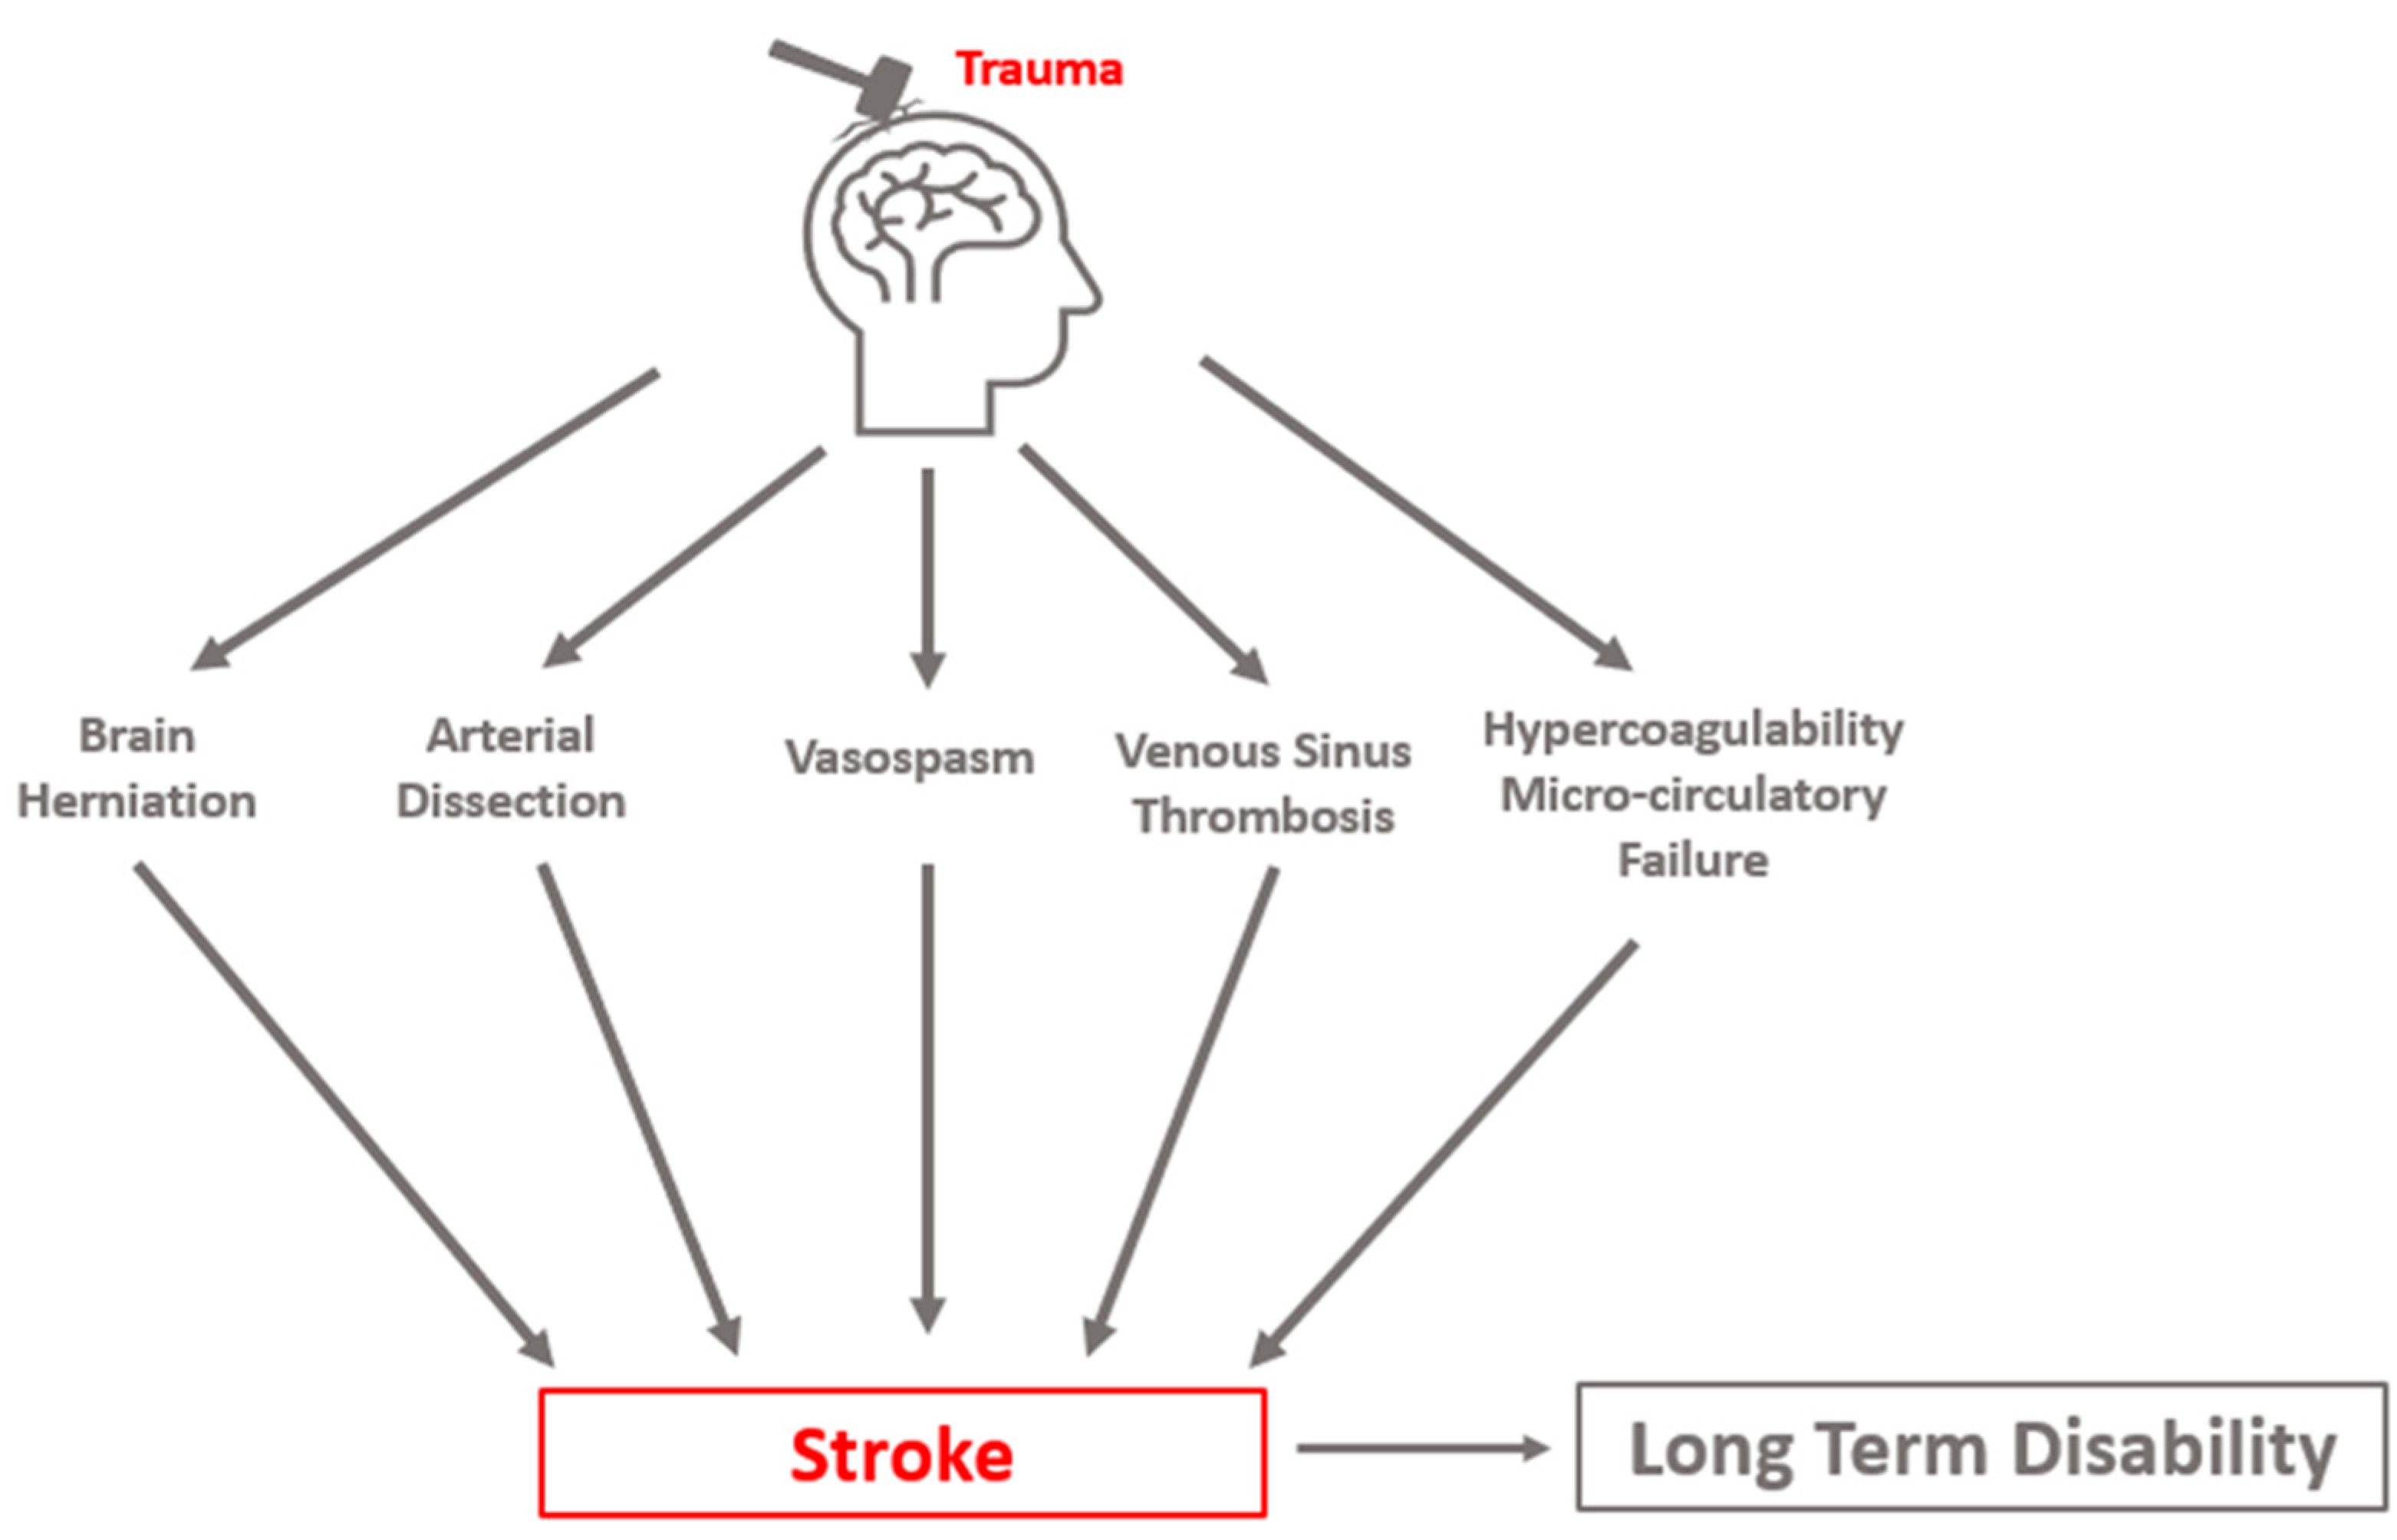

:1. Introduction

1.2. Secondary Brain Injury in Traumatic Brain Injury

1.3. Post-Traumatic Cerebral Infarction: An Important Cause of Secondary Brain Injury

2. Pathophysiology

2.2. Brain Herniation

2.3. Cervical Artery Dissection

2.4. Post-Traumatic Vasospasm

2.5. Cerebral Venous Thrombosis

2.6. Microthrombosis and Microcirculatory Failure